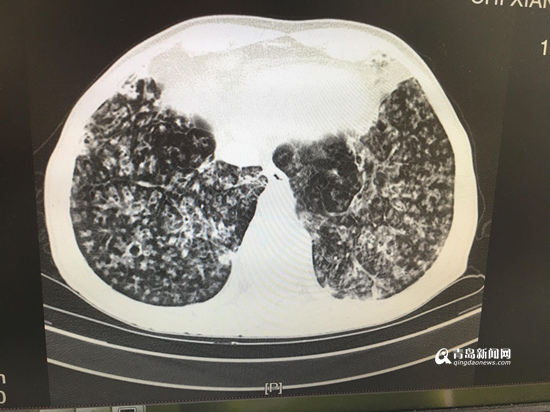

胸部CT顯示病灶彌漫。

根據(jù)患者病情、影像學(xué)檢查結(jié)果,經(jīng)集團(tuán)本部肺部感染診療中心主任兼西院區(qū)呼吸內(nèi)科學(xué)科負(fù)責(zé)人、首席專家劉學(xué)東主任與西院區(qū)呼吸內(nèi)科蘭淑娟主任及專家團(tuán)隊(duì)共同研究、探討,老人被確診為“彌漫性泛細(xì)支氣管炎”(簡(jiǎn)稱“DPB”)。呼吸內(nèi)科蘭淑娟主任說:“DPB通常在40歲左右起病,初期有慢性咳嗽和膿痰,后期則表現(xiàn)為活動(dòng)后呼吸困難且呈進(jìn)行性加重。臨床診斷標(biāo)準(zhǔn)包括必須項(xiàng)目項(xiàng)及參考項(xiàng)目?!北仨氻?xiàng)目三項(xiàng),分別是:持續(xù)咳嗽、咳痰及勞力性呼吸困難;目前或過去有鼻竇炎;胸部X線示兩肺彌漫性散在分布的顆粒樣結(jié)節(jié)狀陰影或胸部CT示兩肺彌漫性小葉中心性顆粒樣結(jié)節(jié)狀陰影。參考項(xiàng)目三項(xiàng),分別是:肺部可聞及啰音;FEV1/FVC<70%,PO2<80mmhg;冷凝集>=1:64。

蘭淑娟主任表示:“該患者除癥狀符合描述,還曾因慢性鼻竇炎看過多年病。患者具有典型的影像學(xué)表現(xiàn),符合DPB臨床診斷標(biāo)準(zhǔn)?!?/p>